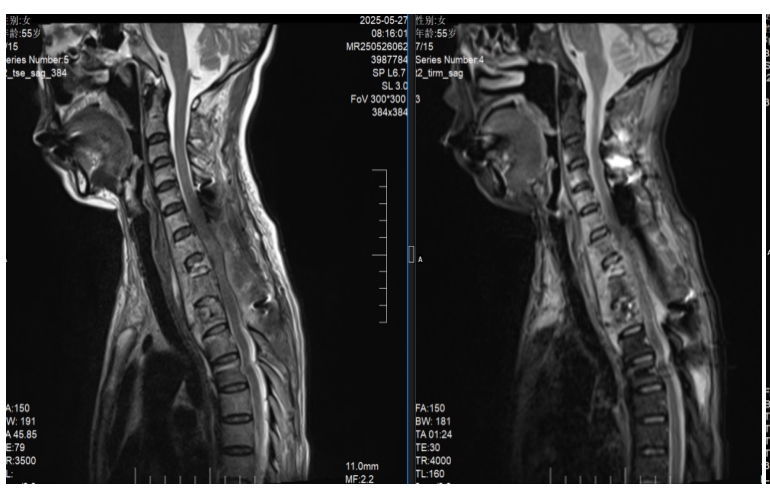

为挽救患者神经功能,抢救患者生命,向伟能迅速组织多学科会诊,为患者量身定制个性化治疗方案:标准四联抗结核治疗、急诊一期颈椎前后路联合病灶清除植骨内固定手术。经过紧急而周密的准备,向伟能团队为艾女士实施了颈椎后路病灶清除椎管减压融合内固定术和颈椎前路病灶清除植骨融合术(图3)。历时6小时,手术团队成功将“蛀骨”病灶一网打尽,并用自体骨填补骨缺损,筑牢脊柱“支撑系统”。得益于成熟的MDT围手术期管理模式,该患者在6小时内顺利完成涵盖9个椎体的融合手术,以及后路联合前路的颈椎病灶清除术,术后患者情况稳定,直接被送返至普通病房,无需转入ICU监护。

图3